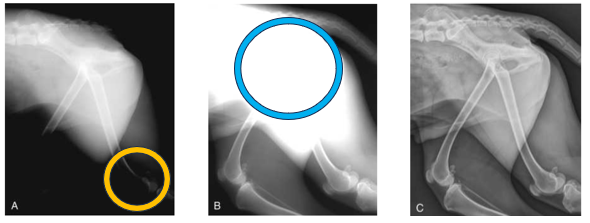

Advantage of CR and DR in regards to exposure - Yellow

The yellow circle indicates overexposure - this radiograph was created using film-based conventional radiography

The x-ray setting for the pelvis and lumber spine is ok but too high for the hindlimbs

Advantage of CR and DR in regards to exposure - Blue

Blue circle indicates underexposure

This radiograph was used using a film-based convention radiography

X-ray settings for the stifles/lower hindlimbs is ok, but not high enough for the pelvis and lumber spine